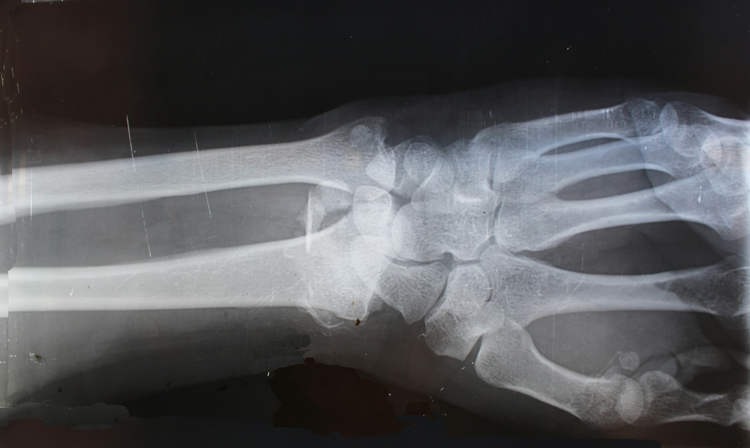

Một trong những ca điển hình là bệnh nhân bị gãy cổ tay do tai nạn sinh hoạt. Thay vì phải phẫu thuật đặt nẹp kim loại, bác sĩ chỉ thực hiện một vết rạch nhỏ dài 3 cm, sau đó tiêm Bone-02 vào vị trí tổn thương.

Toàn bộ quá trình chỉ kéo dài vài phút, và khi tái khám sau ba tháng, vết gãy đã hoàn toàn liền xương, không cần can thiệp thêm. Đặc biệt, bệnh nhân không gặp biến chứng hay phản ứng phụ nào, điều thường thấy ở các ca cấy ghép kim loại truyền thống.